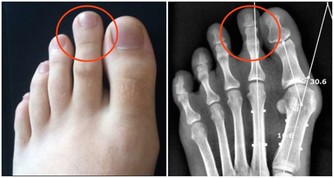

會。家族性高膽固醇血症是全球最常見的家族性遺傳疾病,由於基因突變身體代謝膽固醇的機制,導致壞的膽固醇(低密度脂蛋白膽固醇)濃度變高,罹患早發性心血管疾病的風險是一般成年人的20倍。父母之一若有家族性高膽固醇血症,孩子有50%的遺傳機會,因此,有家族史的高危險群應儘早就醫檢查。